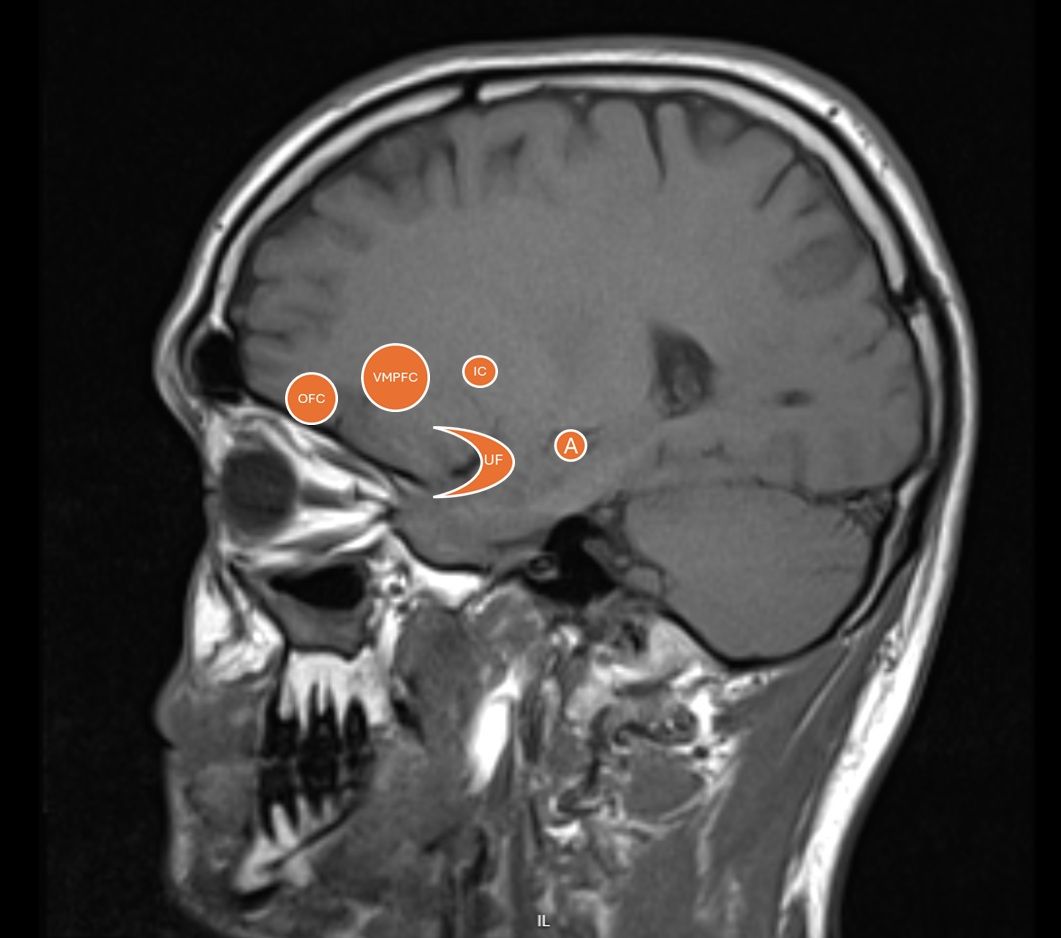

Například velká studie provedená v USA s více než 800 vězni ukázala, že vrazi mají menší objem šedé hmoty v oblastech mozku důležitých pro emoční zpracování (insulární kůra), morální rozhodování (orbitofrontální kůra) a empatii (ventromediální prefrontální kůra). Snížený objem šedé hmoty znamená méně neuronů a gliových buněk, což v těchto oblastech může vést k oslabené schopnosti zpracovávat sociální a morální informace – tedy právě ty, které jsou zásadní pro vcítění do druhých, sebeovládání a chápání důsledků vlastního jednání.

Umístění zmiňovaných oblastí. A - amygdala, IC - insulární kůra, VMPFC - ventromediální prefrontální kůra, OFC - orbitofrontální kůra, UF - fasciculus uncinatus (háčkovitý svazek).

Pokud bychom se ptali, jak je možné, že se někteří lidé mohou lhostejně dopouštět nepředstavitelných krutostí, jedním z klíčových neurobiologických mechanismů, který může tuto schopnost ovlivnit, je propojení mezi ventromediální prefrontální kůrou (vmPfc) a amygdalou – oblastmi mozku, které hrají zásadní roli pro naší schopnost cítit strach, soucit nebo vinu.